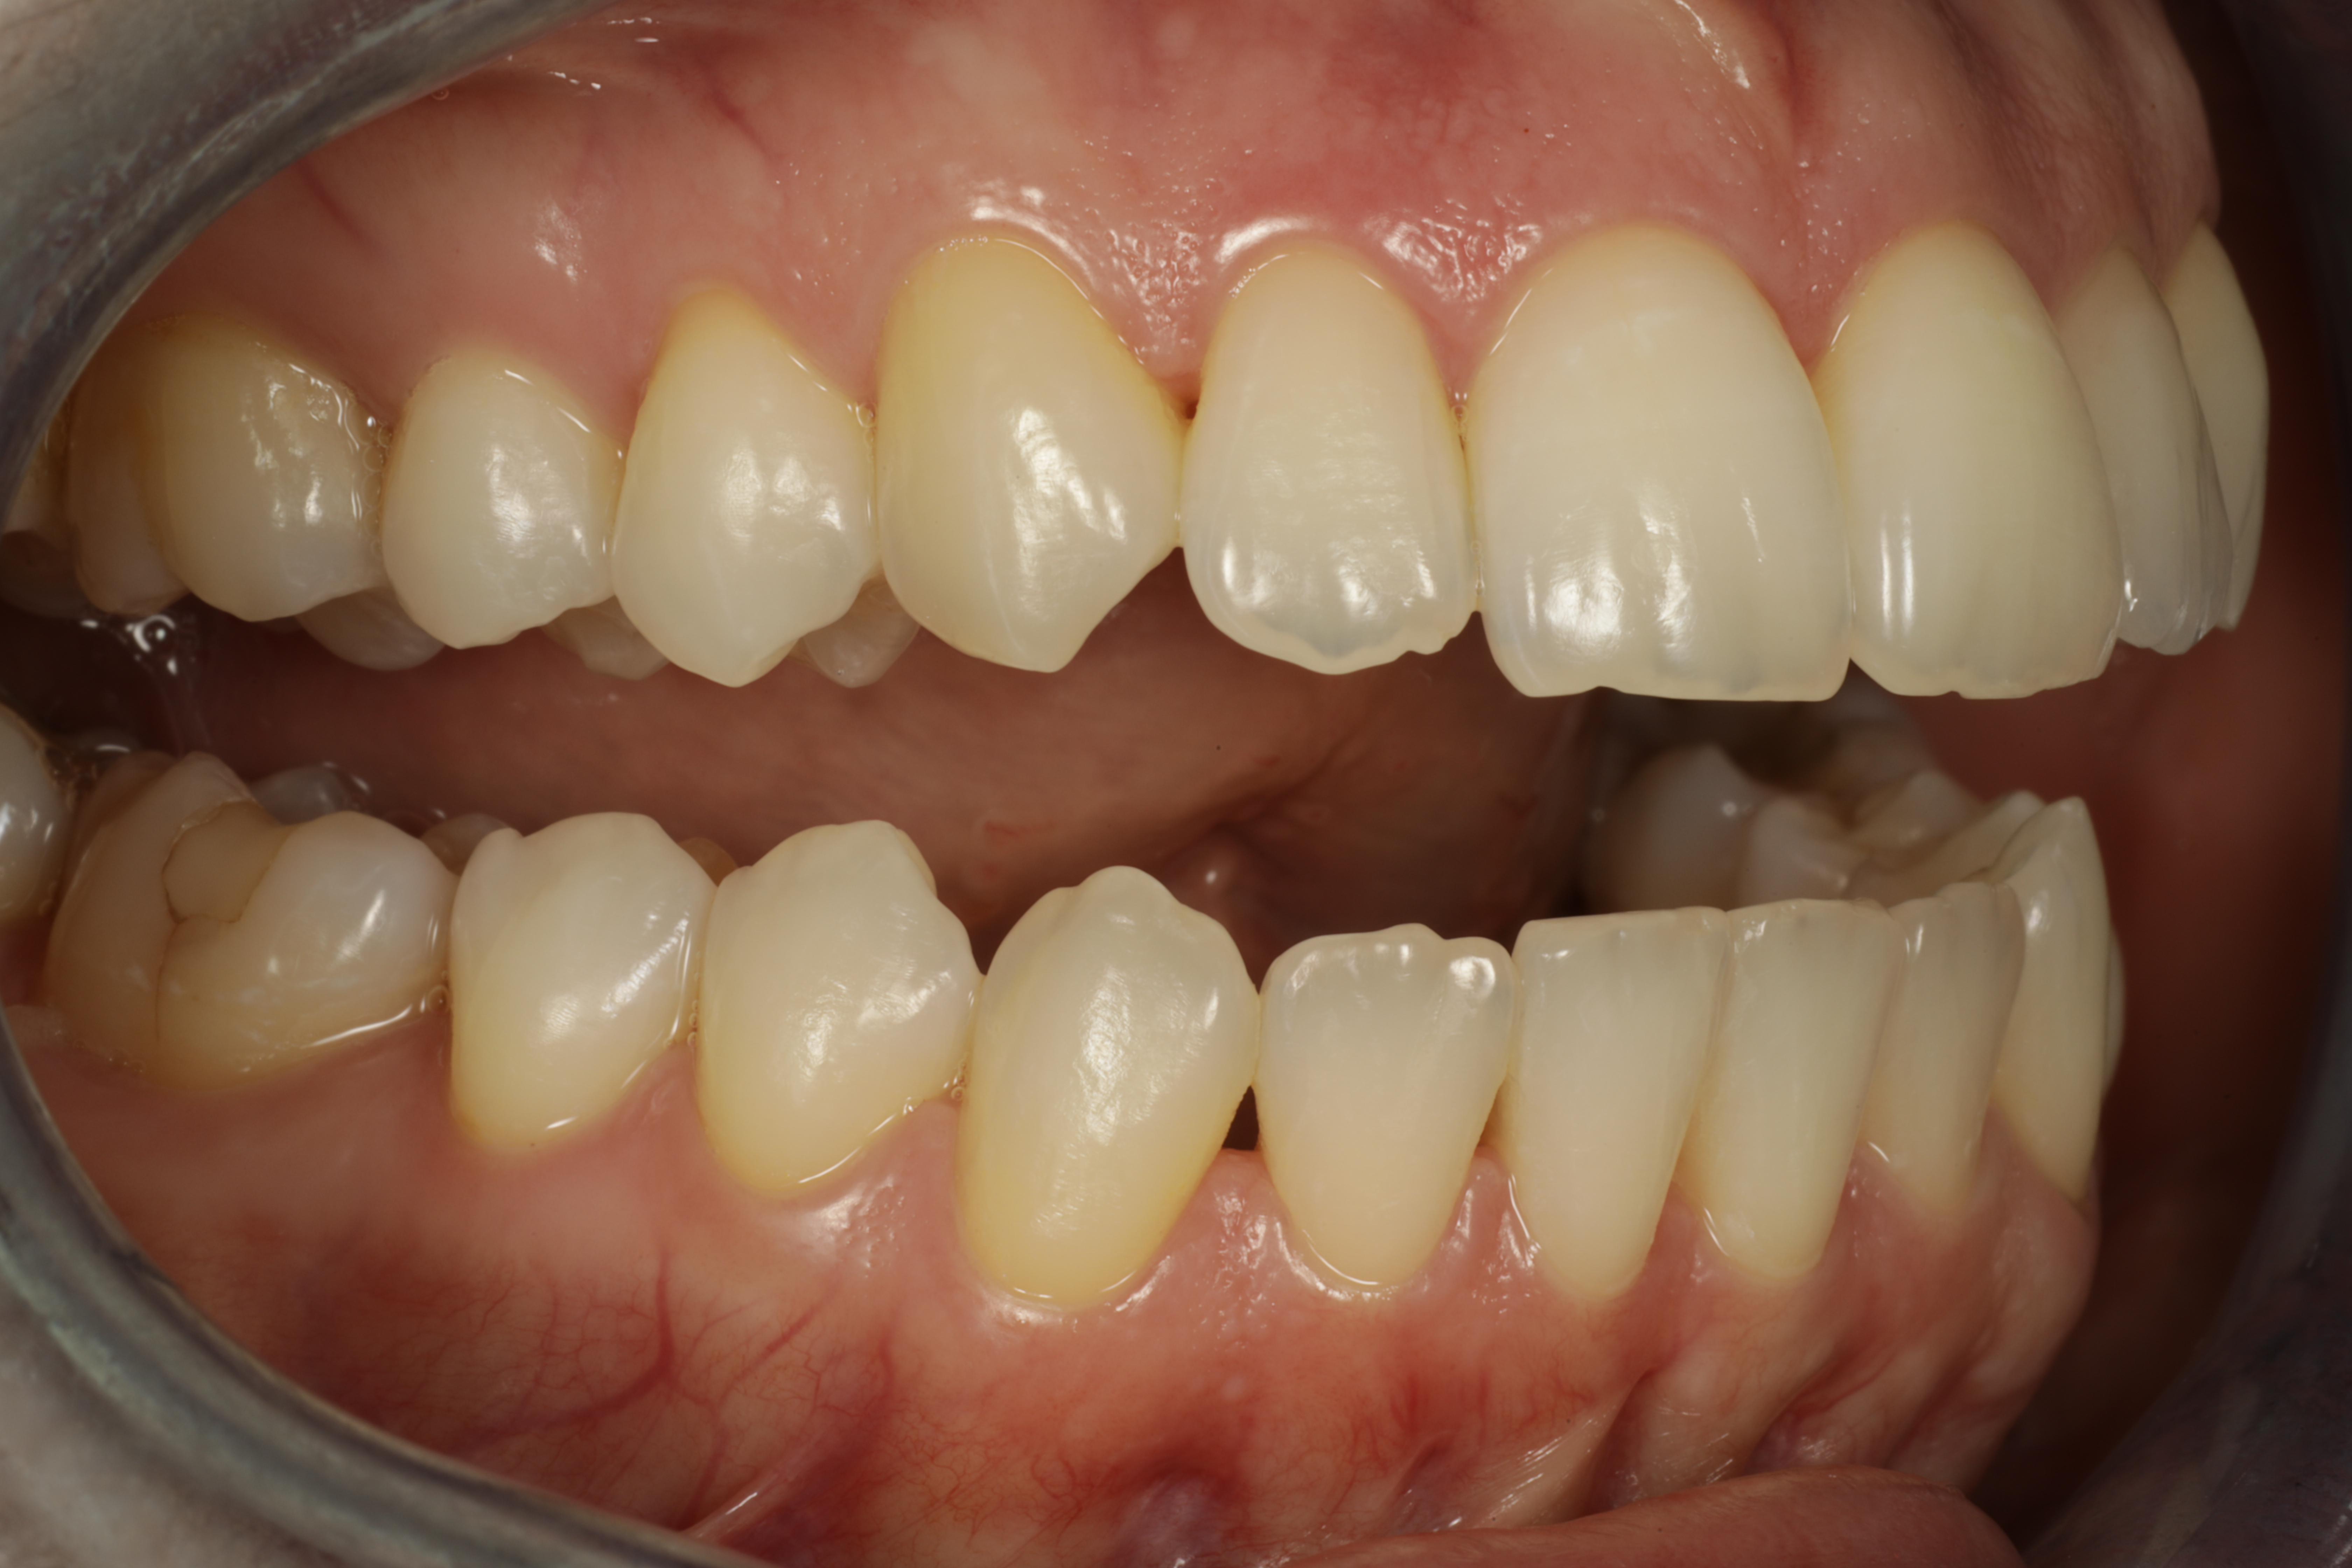

Alla suorittamiani hoitoja ja esimerkkejä siitä minkälaisia purentavirheitä voi korjata.

10 kk hoito (Comprehensive). Aavistus esteettistä muovia lisätty yläkulmahampaisiin hoidon jälkeen.